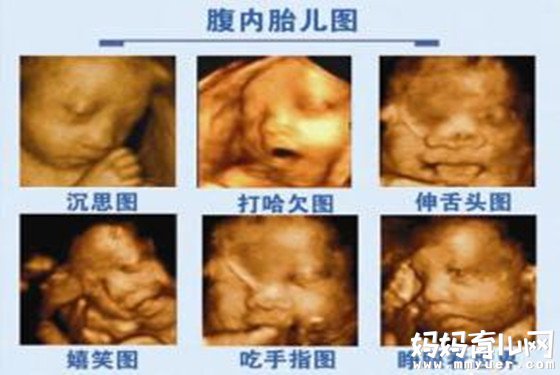

从最初的黑白超一代代的升级为现在的四维彩超,不得不佩服医学科技的发展发达。我们都知道四级彩超可以适时观察胎儿在母体里的一举一动,它更是检测胎儿是否畸形,是否发育健全的关键器具。

话不多说了,下面,就一起回到起点,让我们共同来见证下怀孕八个月胎儿彩超,看看胎儿在这一个月里成长发育改变吧。

怀孕八个月胎儿彩超